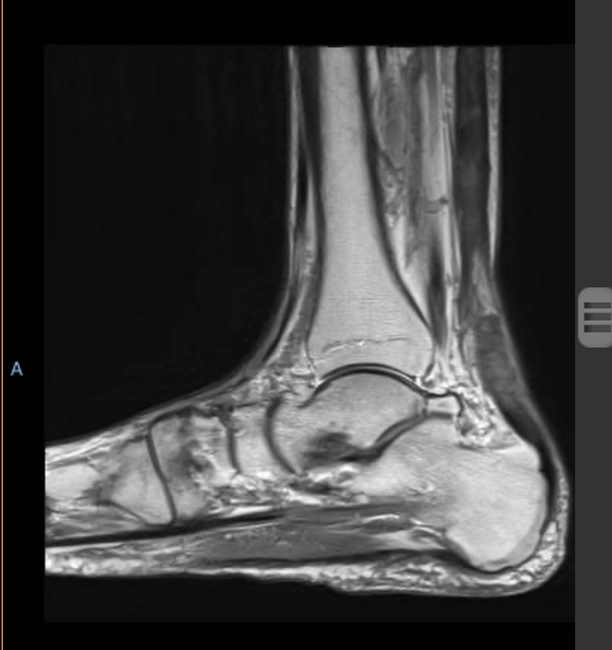

The patient presented to a podiatrist seven weeks after his hospital treatment due to left Achilles pain. On presentation, the pain appeared to be more proximal, but then settled into the Achilles area. On physical exam there was mild thickness or nodularity about 2–3 cm proximal to the insertion of the Achilles with decreased strength and acute balance issues. Magnetic resonance imaging showed a rupture of the Achilles tendon 4.5 cm from the attachment site. Physicians decided on a non-surgical approach including two weeks in a standard fiber glass cast followed by four weeks in a tall controlled ankle motion (CAM) walker with a heel lift. The patient was then transitioned into a sneaker with a carbon graphite plate below his over-the-counter insert modified with a heel lift.